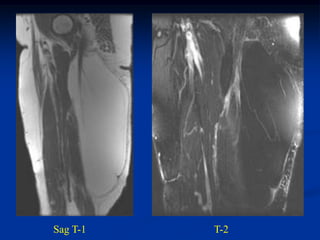

Sag T-1   T-2 FS

Sag T-1   T-2